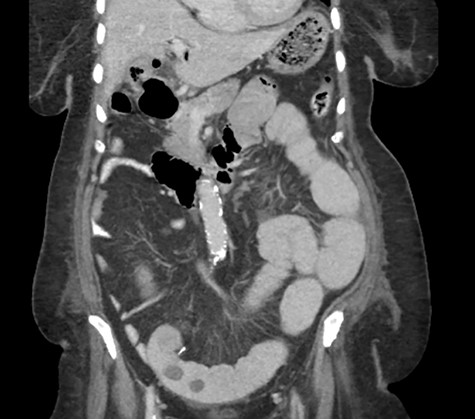

An 81-year-old woman with long history of gallstones was presented to the emergency department with persistent vomiting associated with progressive abdominal distension and inability to pass bowel motion or gases for the past 3 days. Examination showed stable vitals and distended abdomen. A computerized tomography (CT) scan showed high-grade small bowel obstruction in mid-ileum caused by a large impacted gallstone (Fig. 1). There was also a wide neck cholecystoduodenal fistula (Fig. 2).

A CT abdomen and pelvis scan showing a large stone in the small bowel.